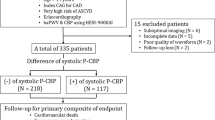

The changes in PWTT (value after PCI minus value before PCI) are shown in Fig. 1 with specific annotation for the radial and femoral access sites (A) and for the LAD and RCA stent sites (B). As shown in Fig. 1(A), the majority of patients (85%) underwent PCI through radial access, and among these, sixteen patients exhibited increased PWTT, six had decreased PWTT, and one had no change after the PCI procedure. Four patients (15%) underwent the procedure through femoral access when the radial access failed, and among these patients, two had increased PWTT while the others had decreased PWTT after the procedure. The mean changed value was 7.9 ms for the radial access group, and −2.5 ms for the femoral access group. Eighteen patients accepted stent implantation in the LAD, which was approximately 67% of the total patients, and the other nine patients (approximately 33%) accepted stent implantation in the RCA, as shown in Fig. 1(B). In the LAD group, twelve patients exhibited an increased PWTT after PCI, while six patients had a decrease. The mean value of PWTT change was 7.2 ms. In the RCA group, six patients exhibited an increase, one remained unchanged and the other two had a decrease in the PWTT, resulting in a mean change of 4.7 ms.

Scatter plots of the changes in PWTT in radial access group and femoral access group (A), as well as in LAD and RCA groups (B). Pink squares represent cases of patients in radial access group and green squares denote cases in femoral access group in section (A). In section (B), the red plots represent values of patients in LAD and the blue plots denote values in RCA. Mean changes of all four groups are shown by the dotted lines with corresponding color.